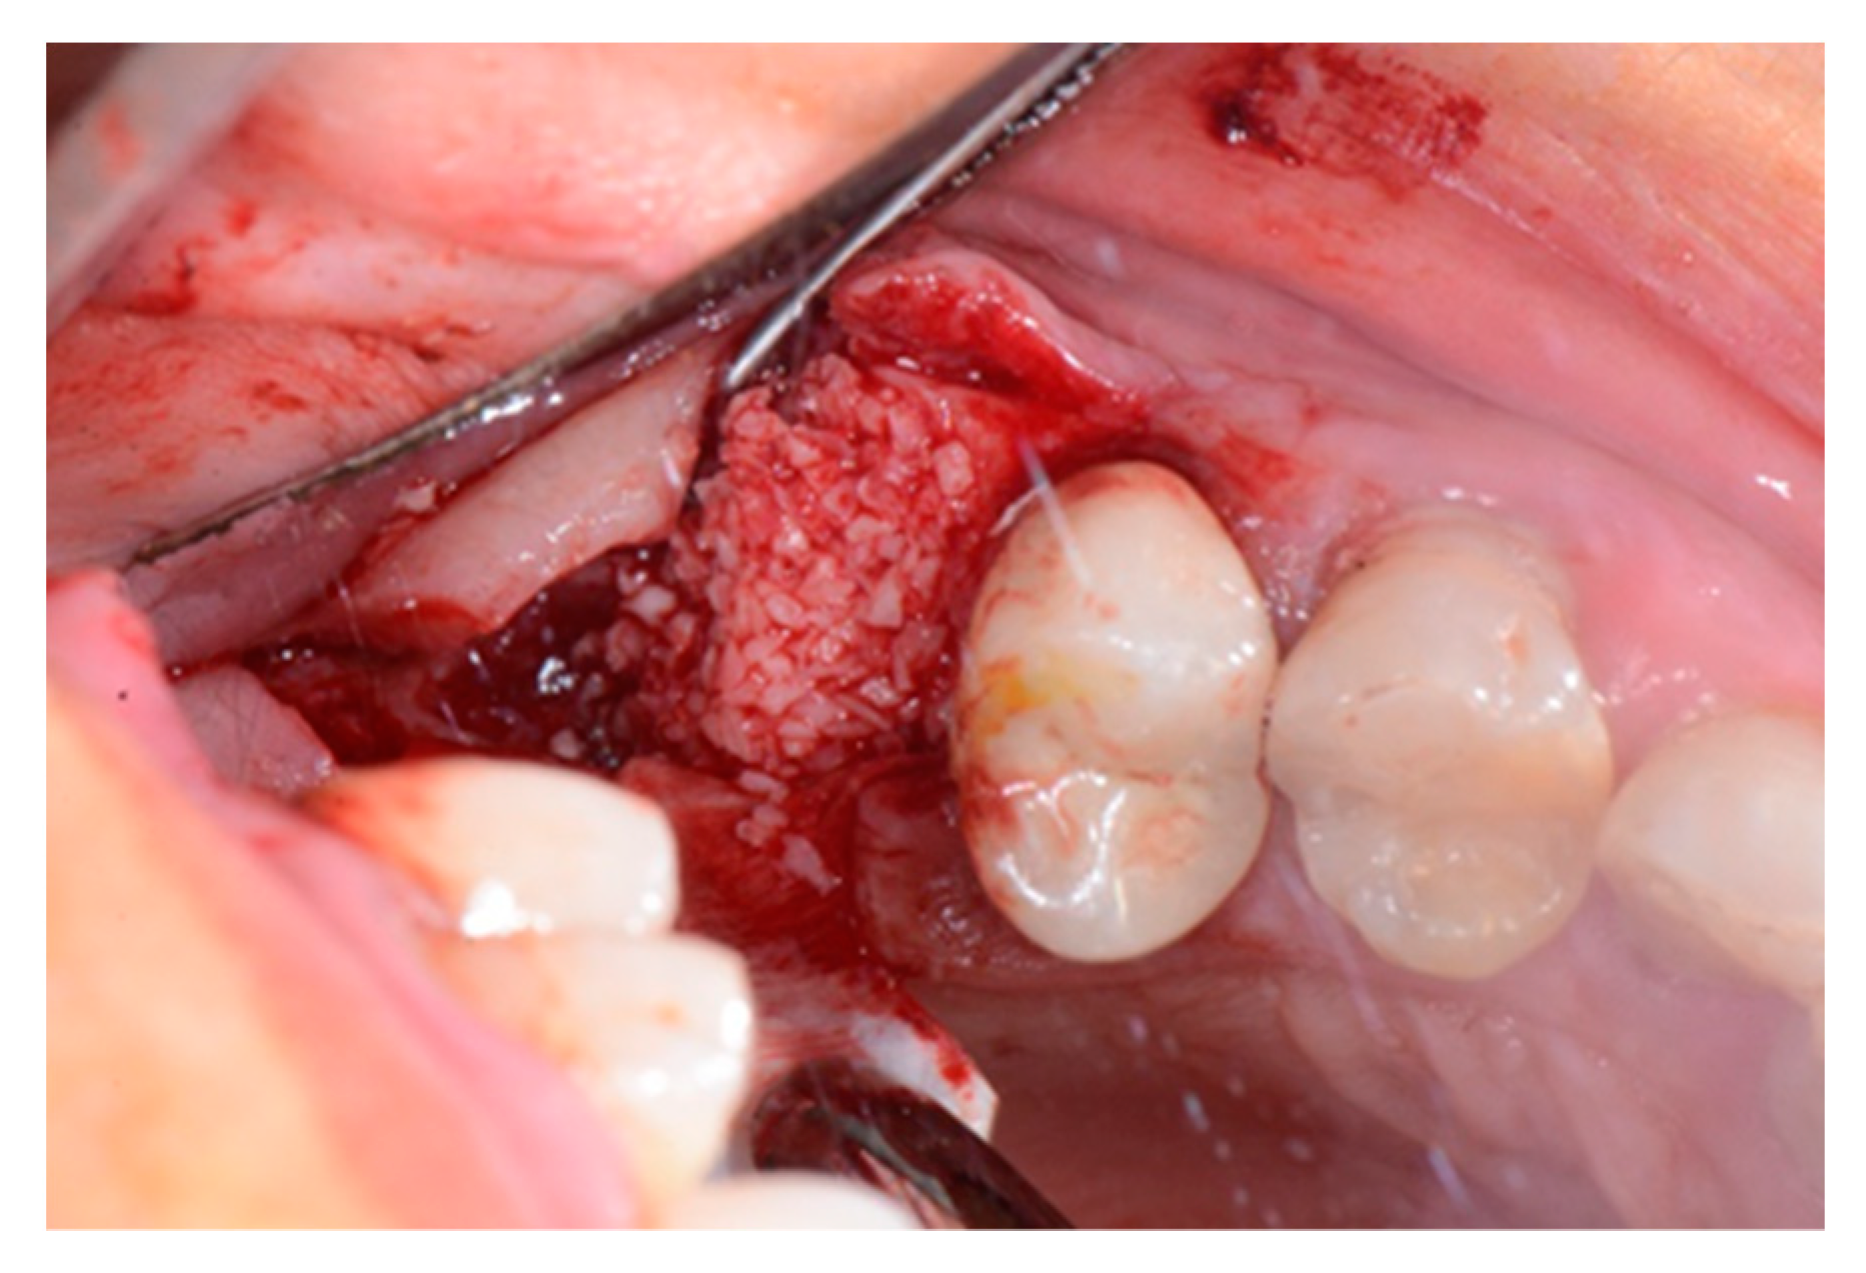

2. Case Report